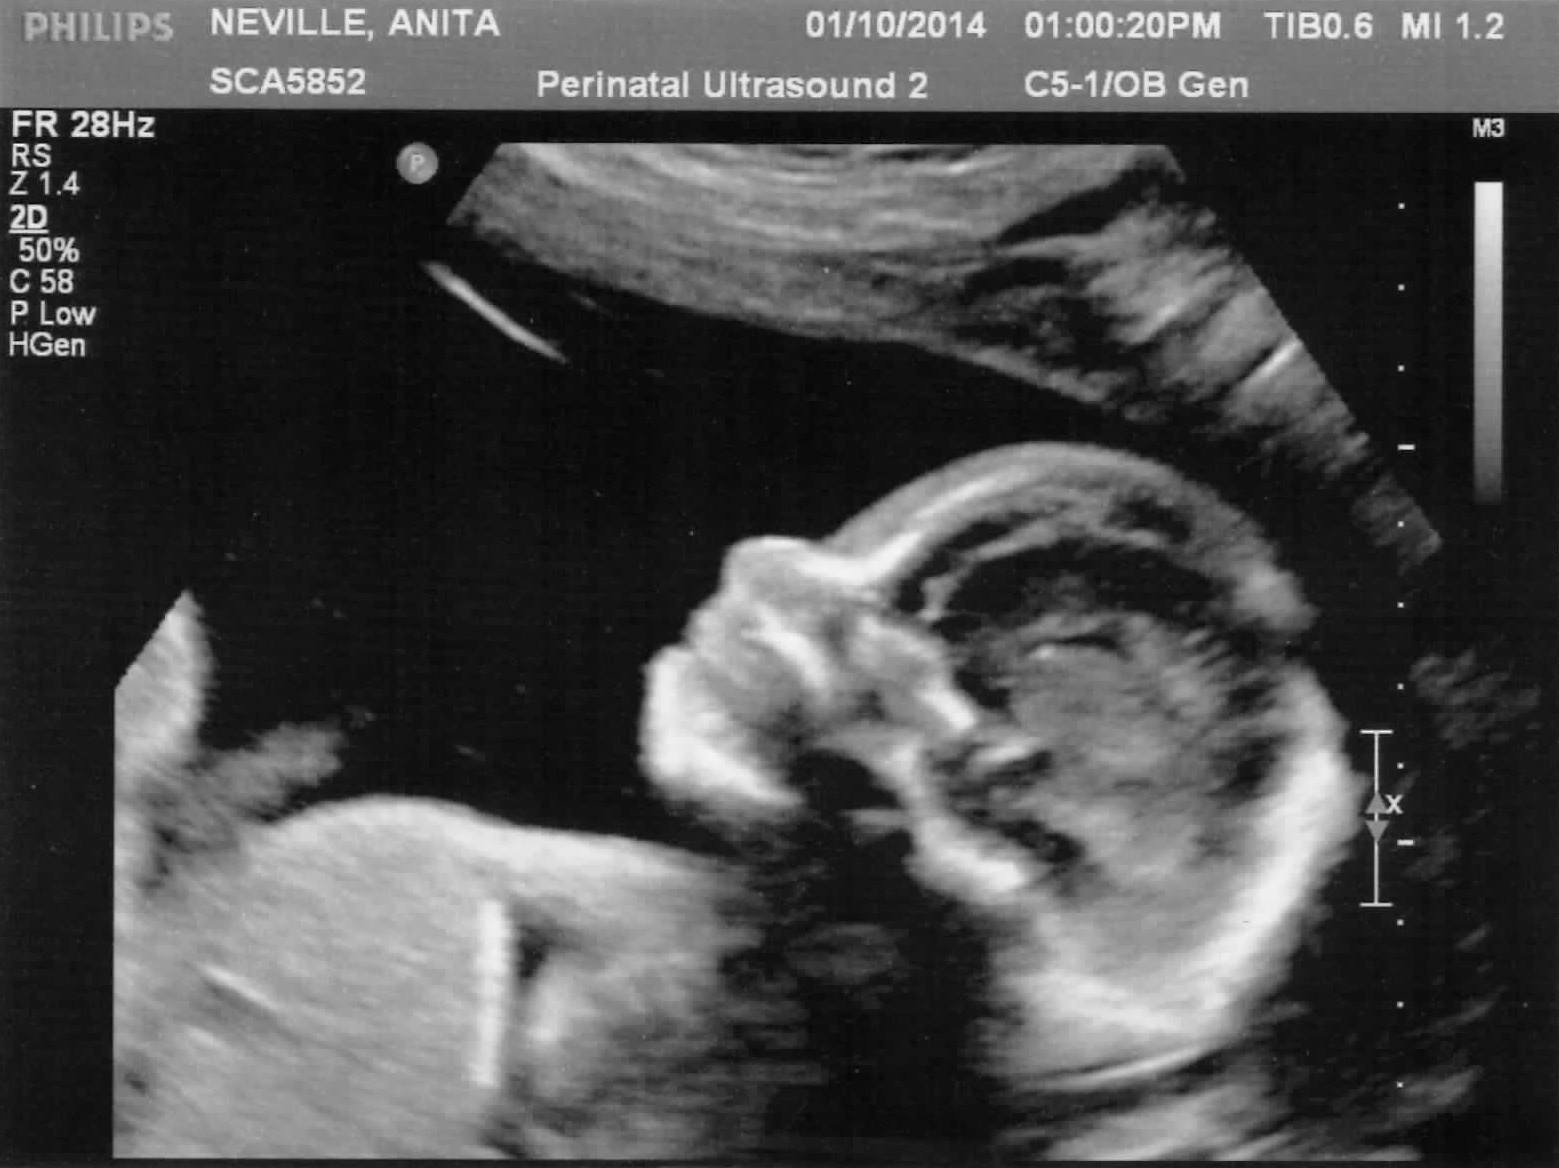

Righto here is my first go at writing a blog. The reason for this blog is help keep everyone updated on little Chloe but also to help my sanity with everything that we experiencing with normal parent life but also coping with the journey that we have been given. I want to confirm I know that we are very lucky …